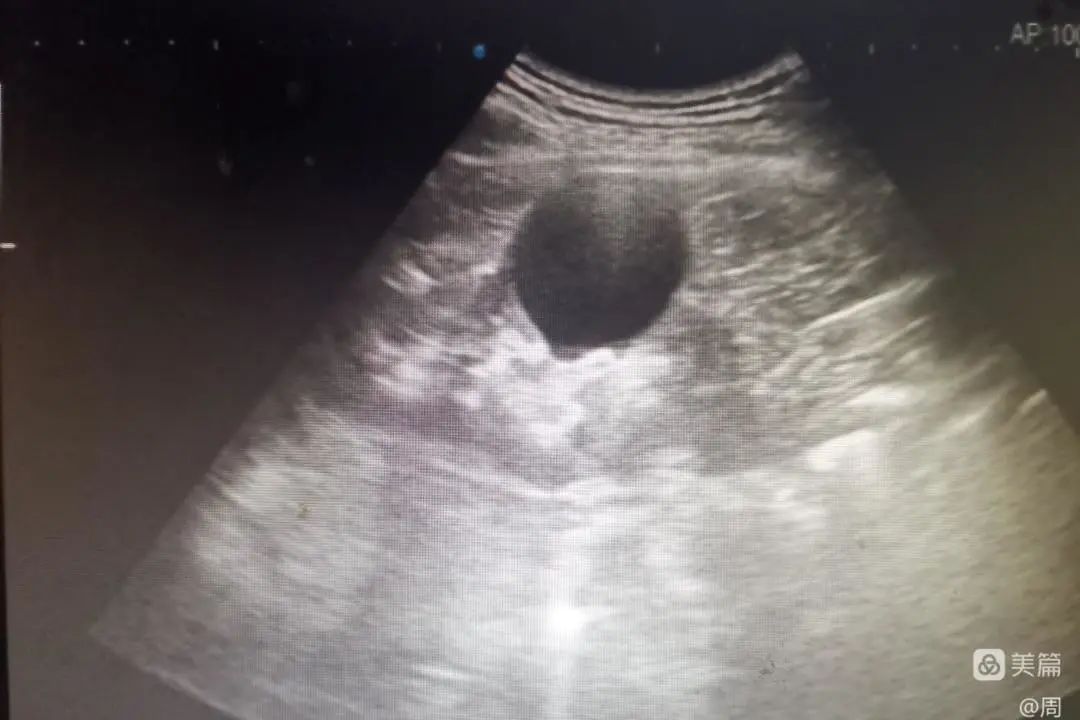

7月14日,龙泉驿区中医医院超声科成功实施首例肾囊肿硬化治疗。患者男,57岁,因左侧膝关节滑膜炎入院做常规彩超检查,发现大小约4.5cmx5.0cm的右肾囊肿,肾实质受压,囊肿无分隔,初步考虑为单纯性囊肿。

术前囊肿大小